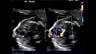

Prenatal Evaluation of Cardiac Function

Elena Sinkovskaya, M.D., Ph.D., RDMS, RDCS